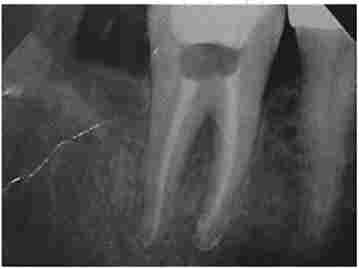

перше відвідування пацієнта включає підготовчий етап. Препарують зуб, розробляють гирла кореневих каналів, створюють прямолінійний доступ в канали. Поетапно евакуюють розпад пульпи з каналів. Виконують ендодонтичне лікування. Промивають канали, здійснюють іригацію кореневого каналу розчинами на основі ЕДТА, гіпохлориту натрію, ферментами з антибіотиками, його розширюють, формують з використанням ендодонтичного інструменту (рис. 6.2). В результаті видаляється біоплівка зі стінок кореневого каналу, змащений шар. Канал промивають, сушать і тимчасово пломбують препаратами з гідроксидом кальцію, зуб герметично закривають на 7-14 діб.

Візіограмма зуба 4.6. Контроль проходження кореневих каналів з ендоінструментамі

Мал. 6.2. Візіограмма зуба 4.6. Контроль проходження кореневих каналів з ендоінструментамі